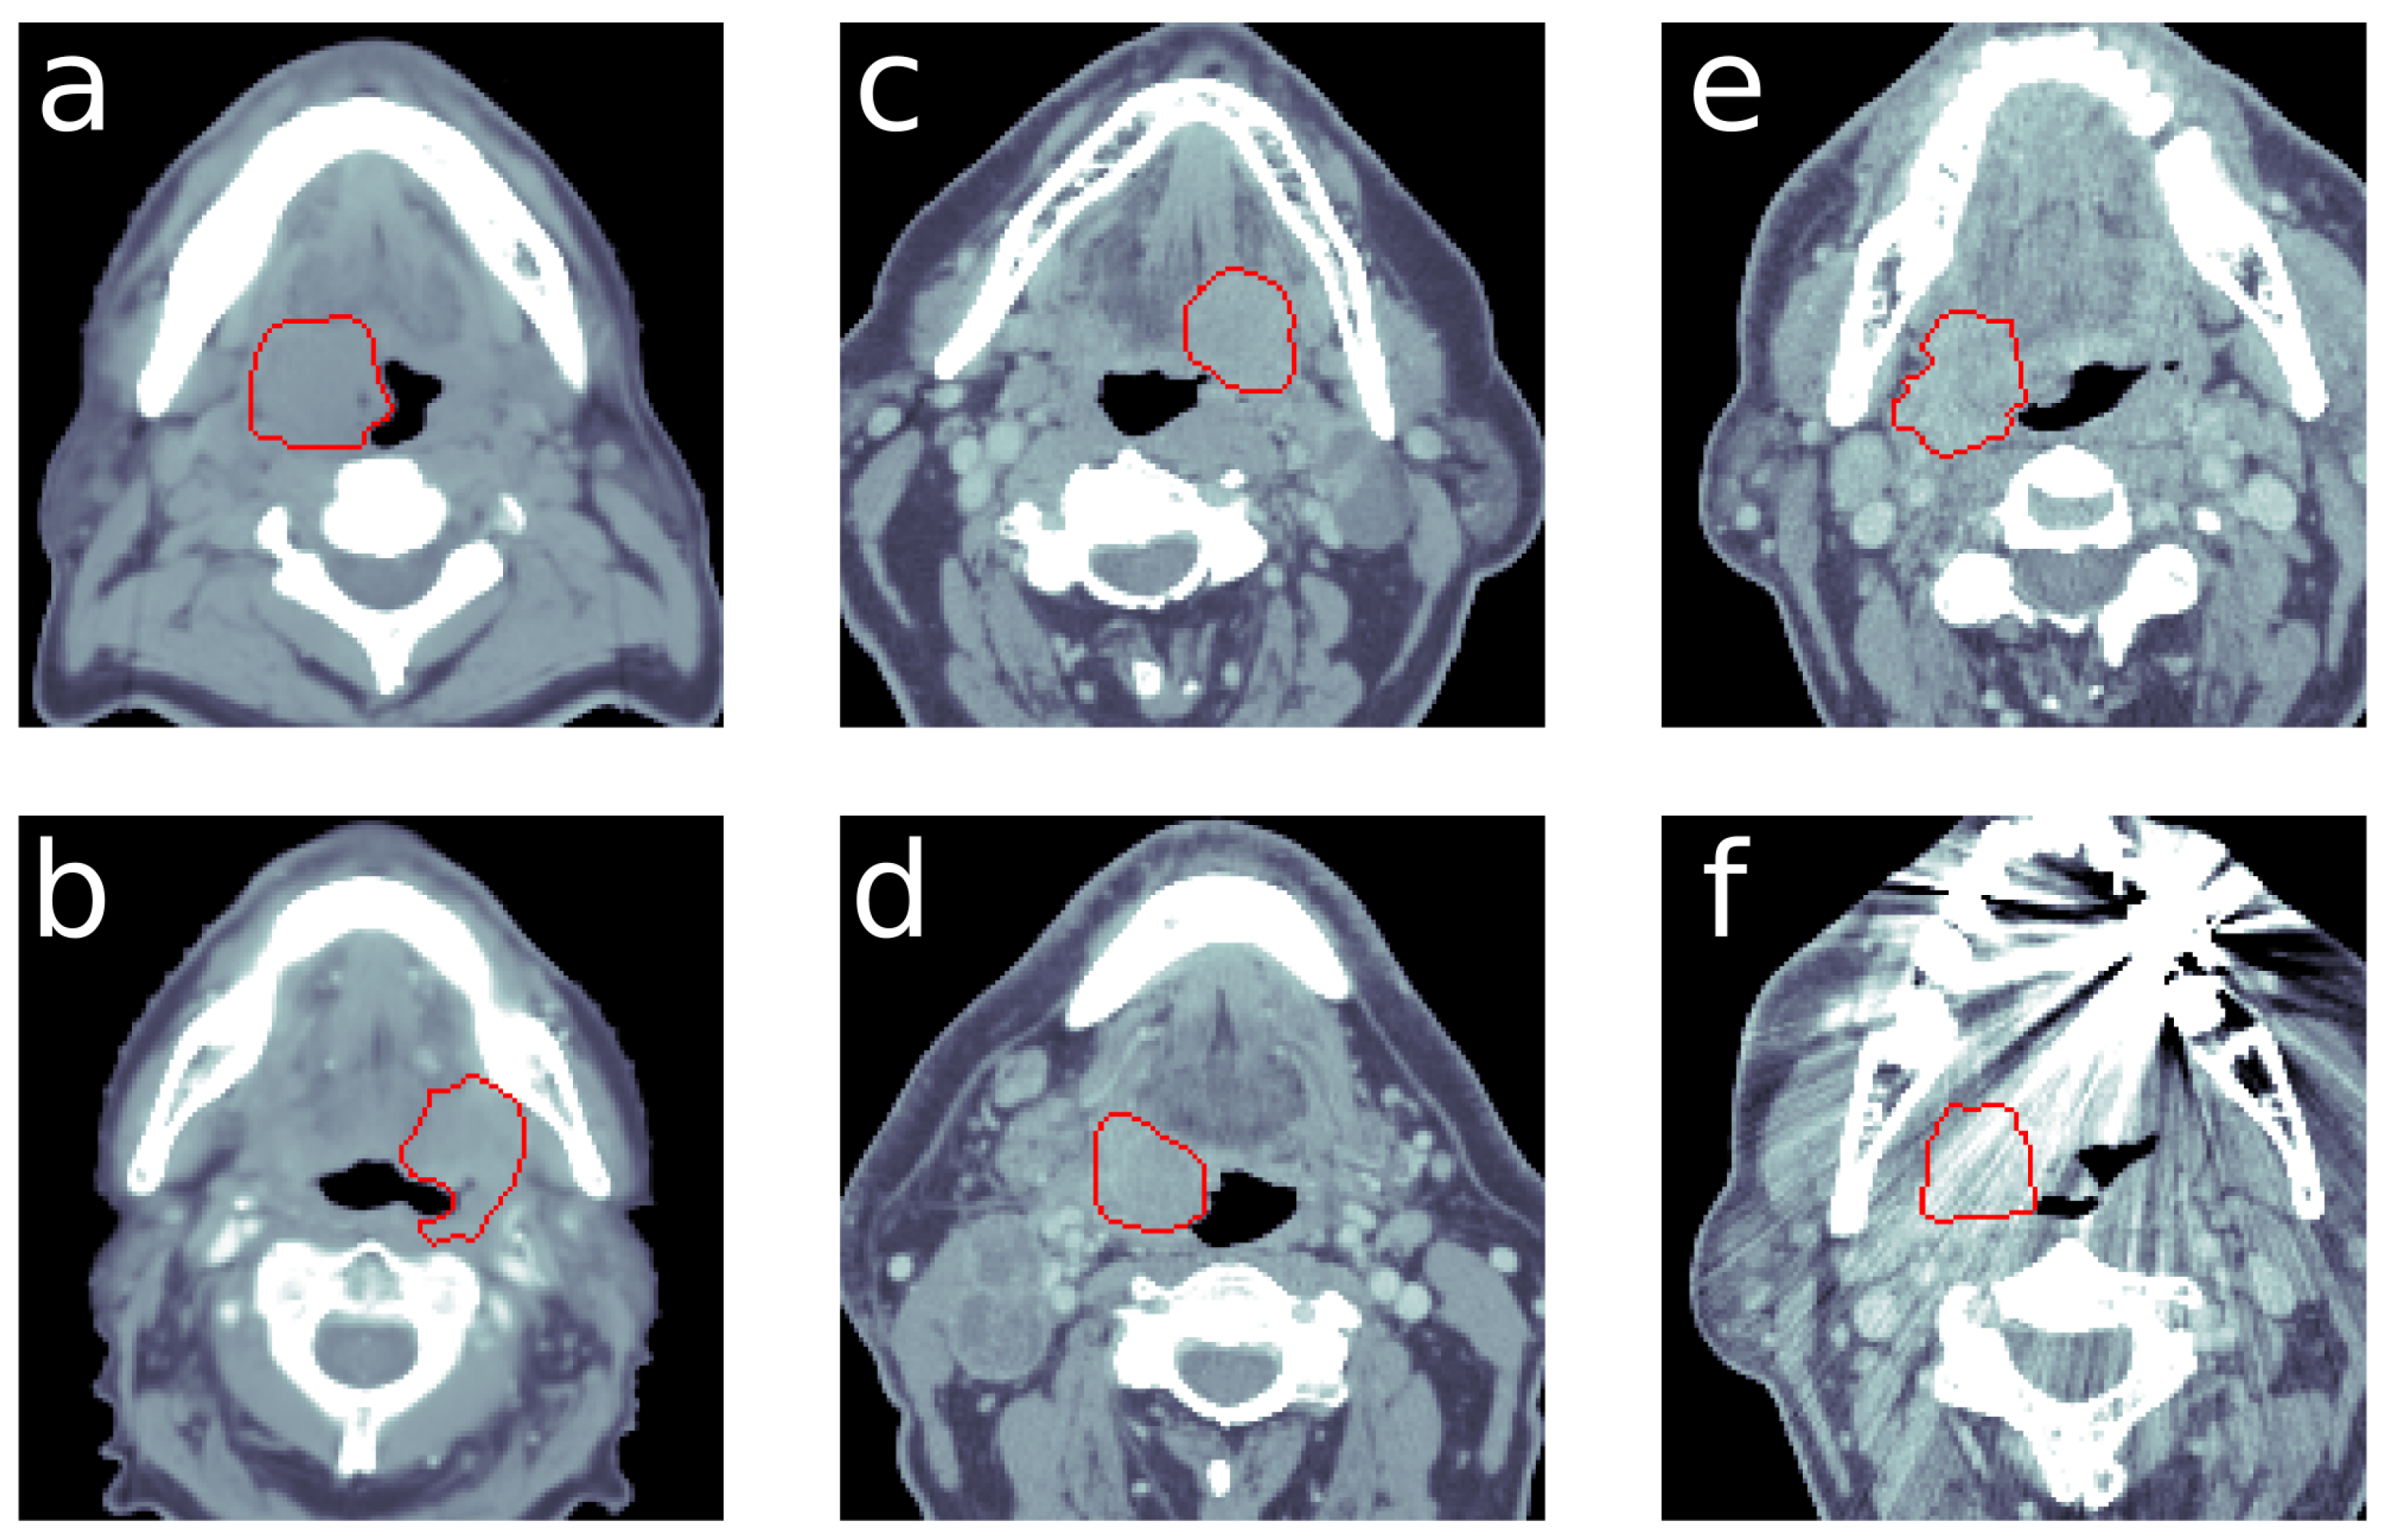

2.1. Data